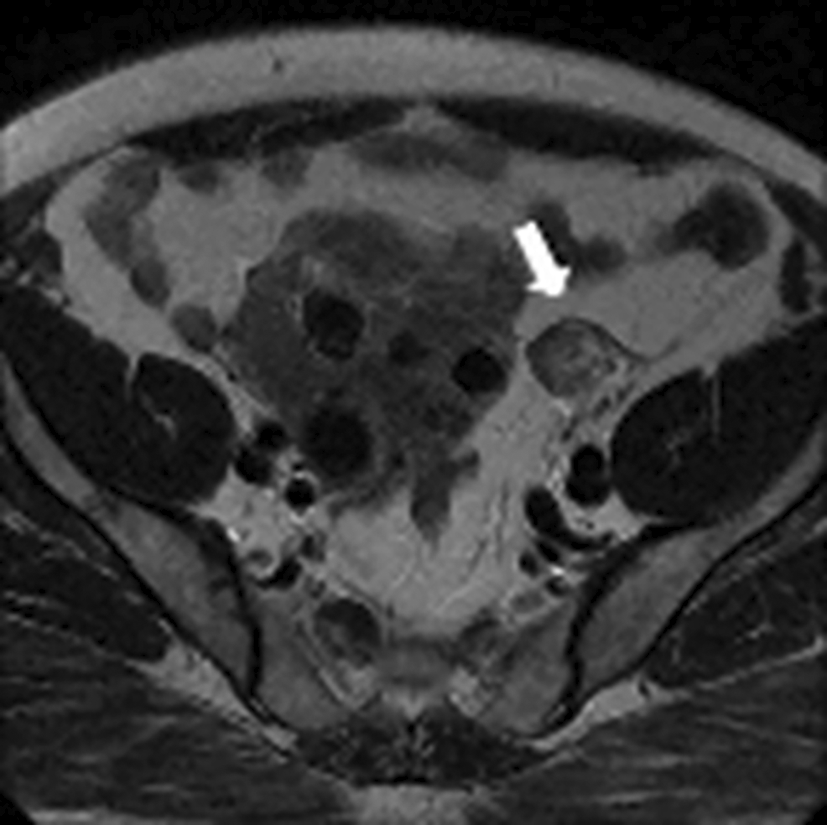

Testosteronemia was at 9.22 nmol/l with normal levels of SDHEA (873 ng/ml). Lab tests revealed a normal basic cortisol level with no findings suggestive of cushing’s syndrome. A Thoraco-abdominopelvic CT was performed showing a 30mm right adrenal mass with spontaneous density at 7 HU and an absolute wash out at 35% suggestive of an adenoma. Pelvic MRI revealed a solid left ovarian mass with heterogeneous signal on T2 with an intermediate risk time intensity curve (B) on dynamic contrast enhancement, classified as ORADS category 4 ( Figure 12).